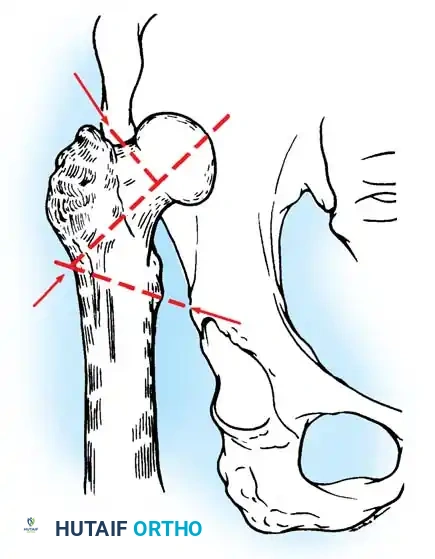

The surgical management of protrusio acetabuli is technically demanding and relies on three non-negotiable biomechanical principles:

1. Restoration of the Anatomic Hip Center: The hip center of rotation must be lateralized and brought inferiorly to its true anatomic position to restore abductor mechanics and minimize joint reactive forces.

2. Peripheral Rim Fixation: The implant must be supported by the intact, structurally sound peripheral rim of the acetabulum, bypassing the deficient medial wall.

3. Medial Wall Reconstruction: Cavitary and segmental defects of the medial wall must be reconstituted, typically utilizing impaction bone grafting (autograft from the resected femoral head or allograft).